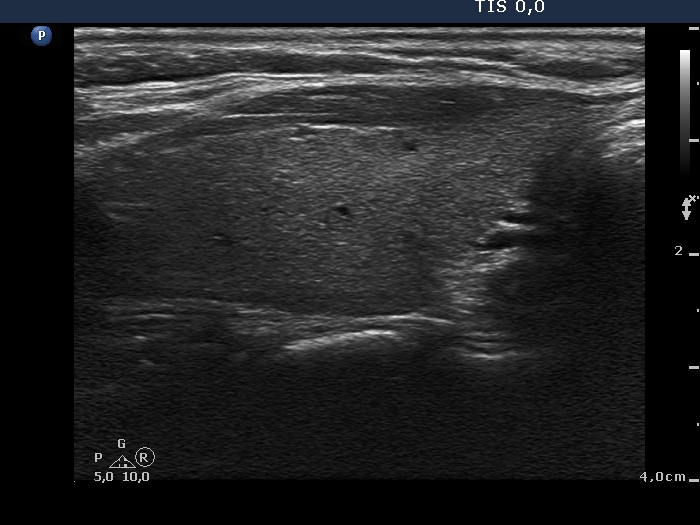

Ultrasonography. The right thyroid was moderately hypoechogenic without any circumscribed lesions. The left thyroid was removed. There were several enlarged lymph nodes in the right submandibular area. The largest one presented two discrete, more hypoechogenic intranodal lesions and a regular hilum.

Comment. This is an unusual case, the nodes (particularly those presented in the video) seem to be benign, reactive-type ones.